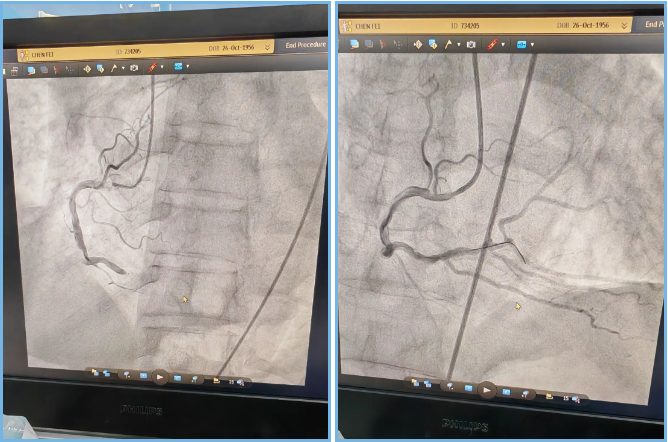

7:47,抵达医院后陈叔就被立刻送入导管室开展手术。导管室医务人员已准备就绪,心脏中心介入团队第一时间对陈叔进行冠状动脉造影检查发现,陈叔曾进行过支架植入手术,此次更是发现原支架附近血管完全堵塞,严重影响了心跳和血压,生命危在旦夕。心脏中心刘国勇主任医师和张铭华博士等组成的手术团队立刻为陈叔进行RCA药物球囊扩张术,导丝通关闭塞病变处。

8:34,成功开通了陈叔此次心梗的罪犯血管,从抵达医院到开通血管仅用47分钟,赢得了时间,成功将陈叔从“鬼门关”前拉了回来。

▲ 术前术后造影图对比